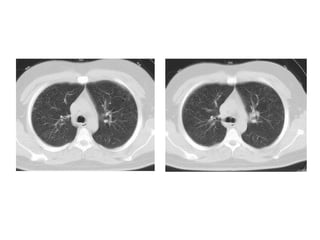

A, Unenhanced axial high-resolution CT through left mid (A) and lower (B) lung

show peripheral honeycombing, which is greatest in lower lobe,

accompanied by traction bronchiectasis and scattered peripheral reticular

opacities. Honeycombing is most prominent feature in this patient, typical for

idiopathic pulmonary fibrosis